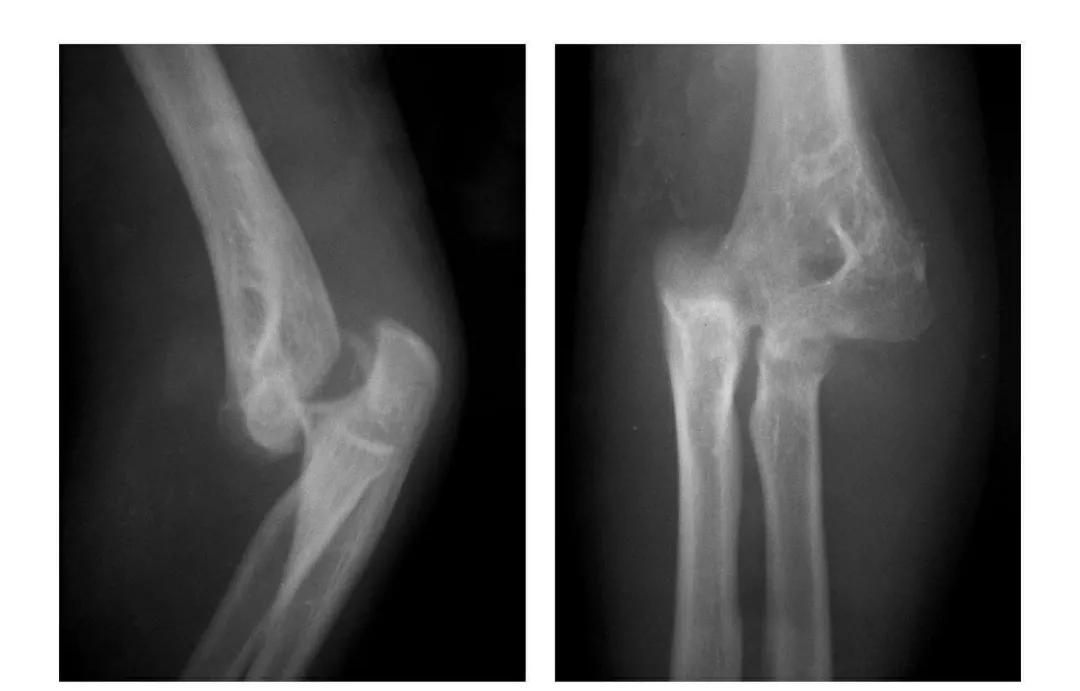

肱骨下端双髁骨折

例1:肱骨内髁及外髁骨折,该两髁骨块均呈向内、外翻转移位。

例2:肱骨内上髁Ⅲ度骨折并外上髁撕脱骨折。

例3:肱骨内上髁Ⅳ度骨折并外上髁撕脱骨折。